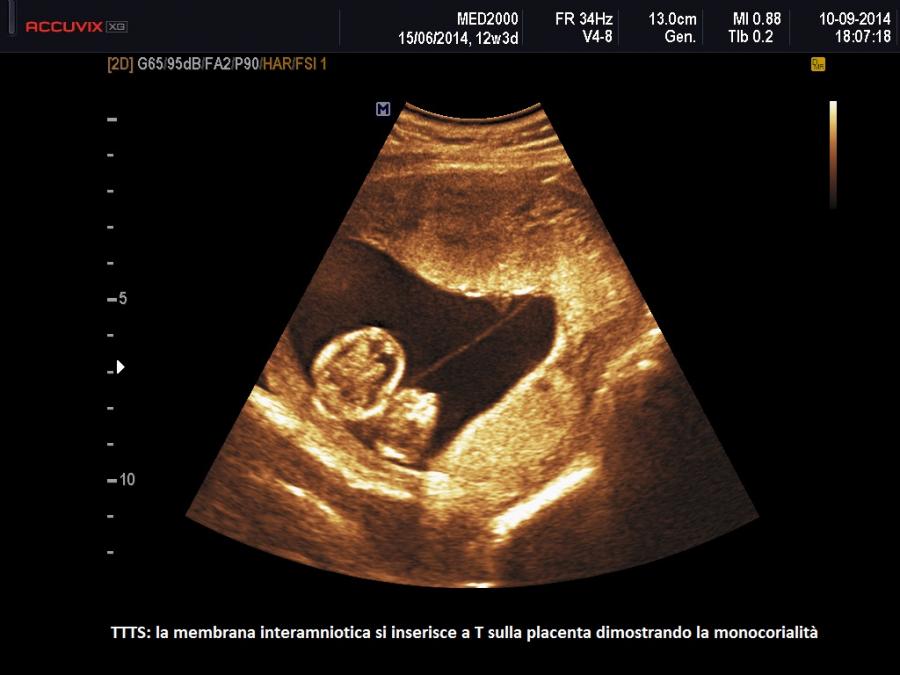

La diagnosi di sindrome da trasfusione feto-fetale è ecografica.

Prerequisiti essenziali per il sospetto diagnostico di TTTS sono:

A 11-14 settimane si sospetta una TTTS quando: